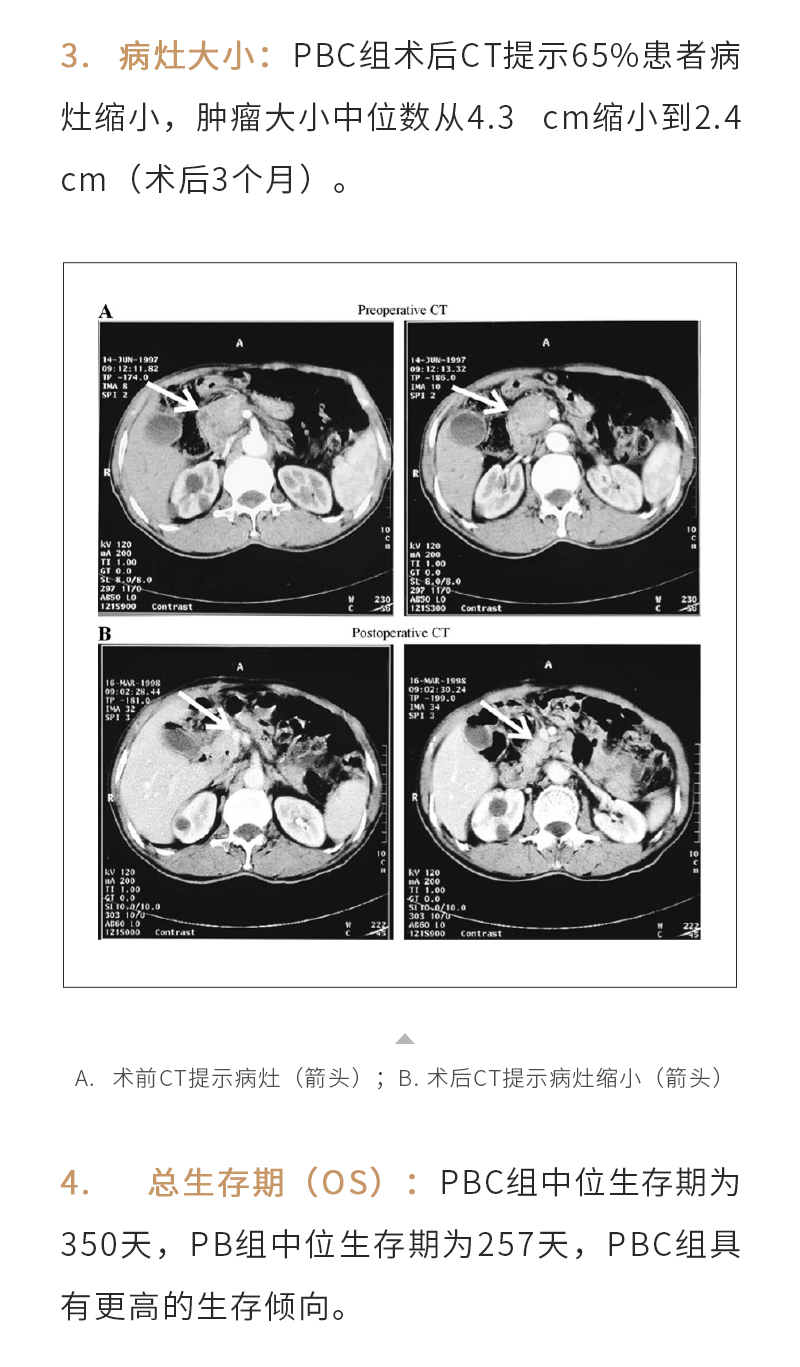

冷冻消融治疗胰腺癌——【海杰亚科研资讯】第265期